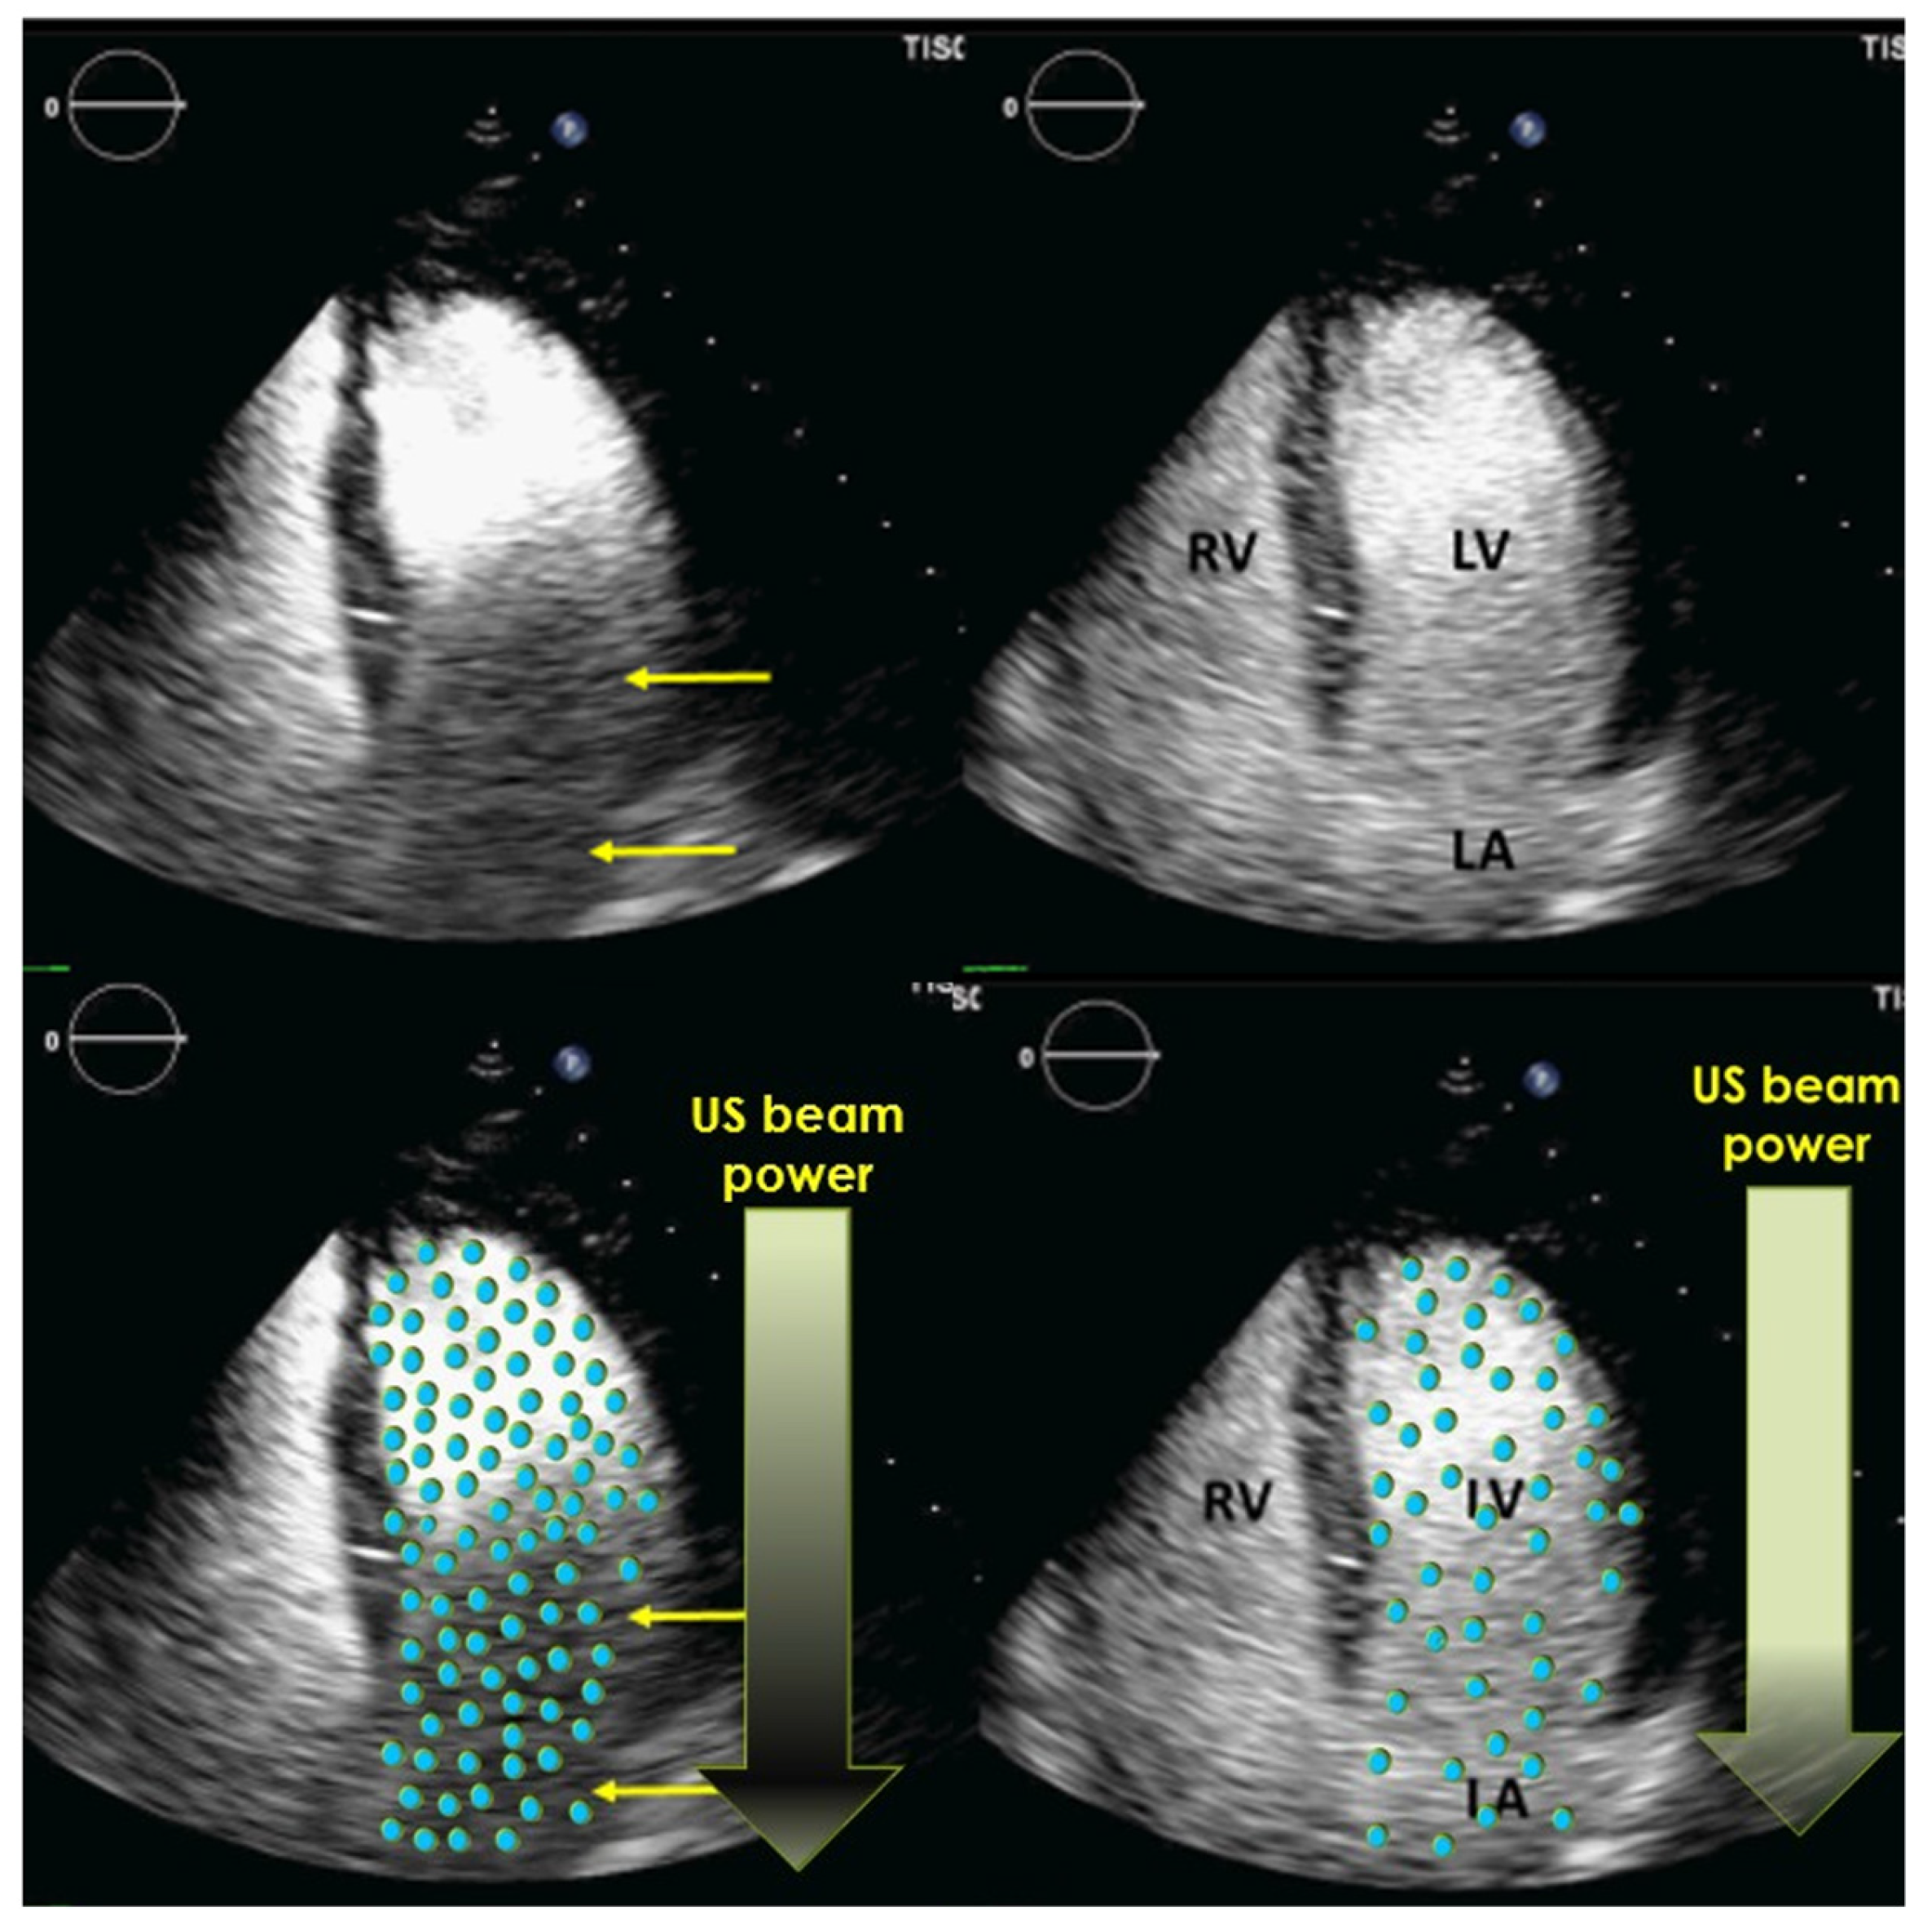

4.3. Optimization of LV Opacification

4.4. How to Avoid Foreshortened Imaging Planes